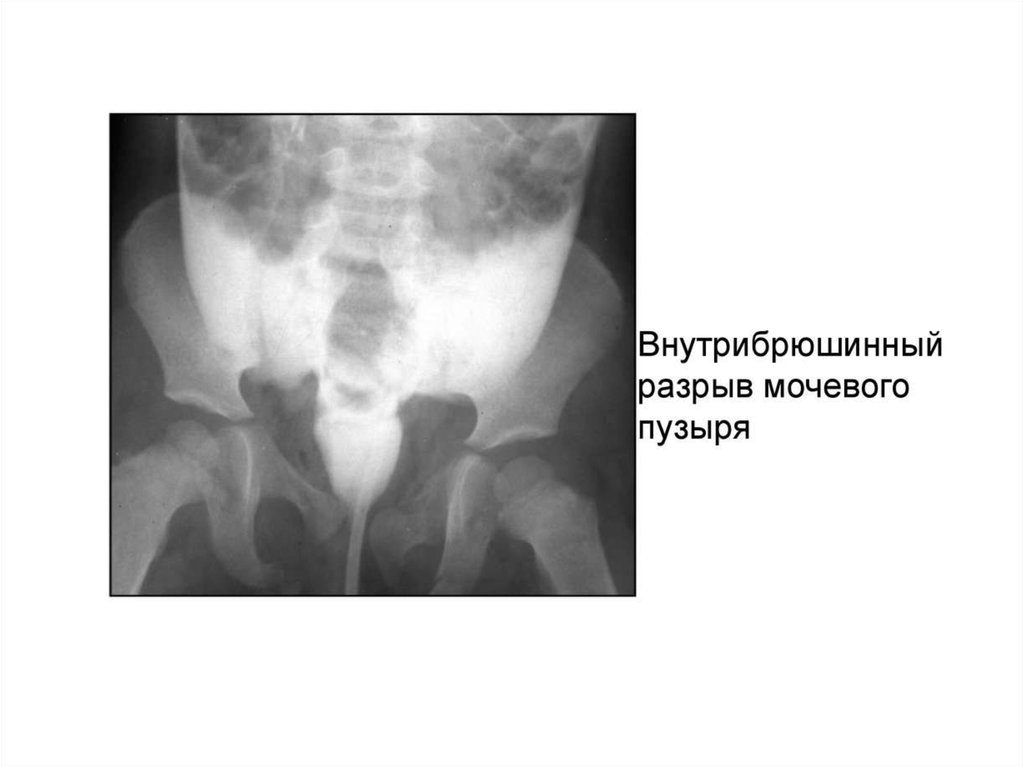

Повреждение органов брюшной полости